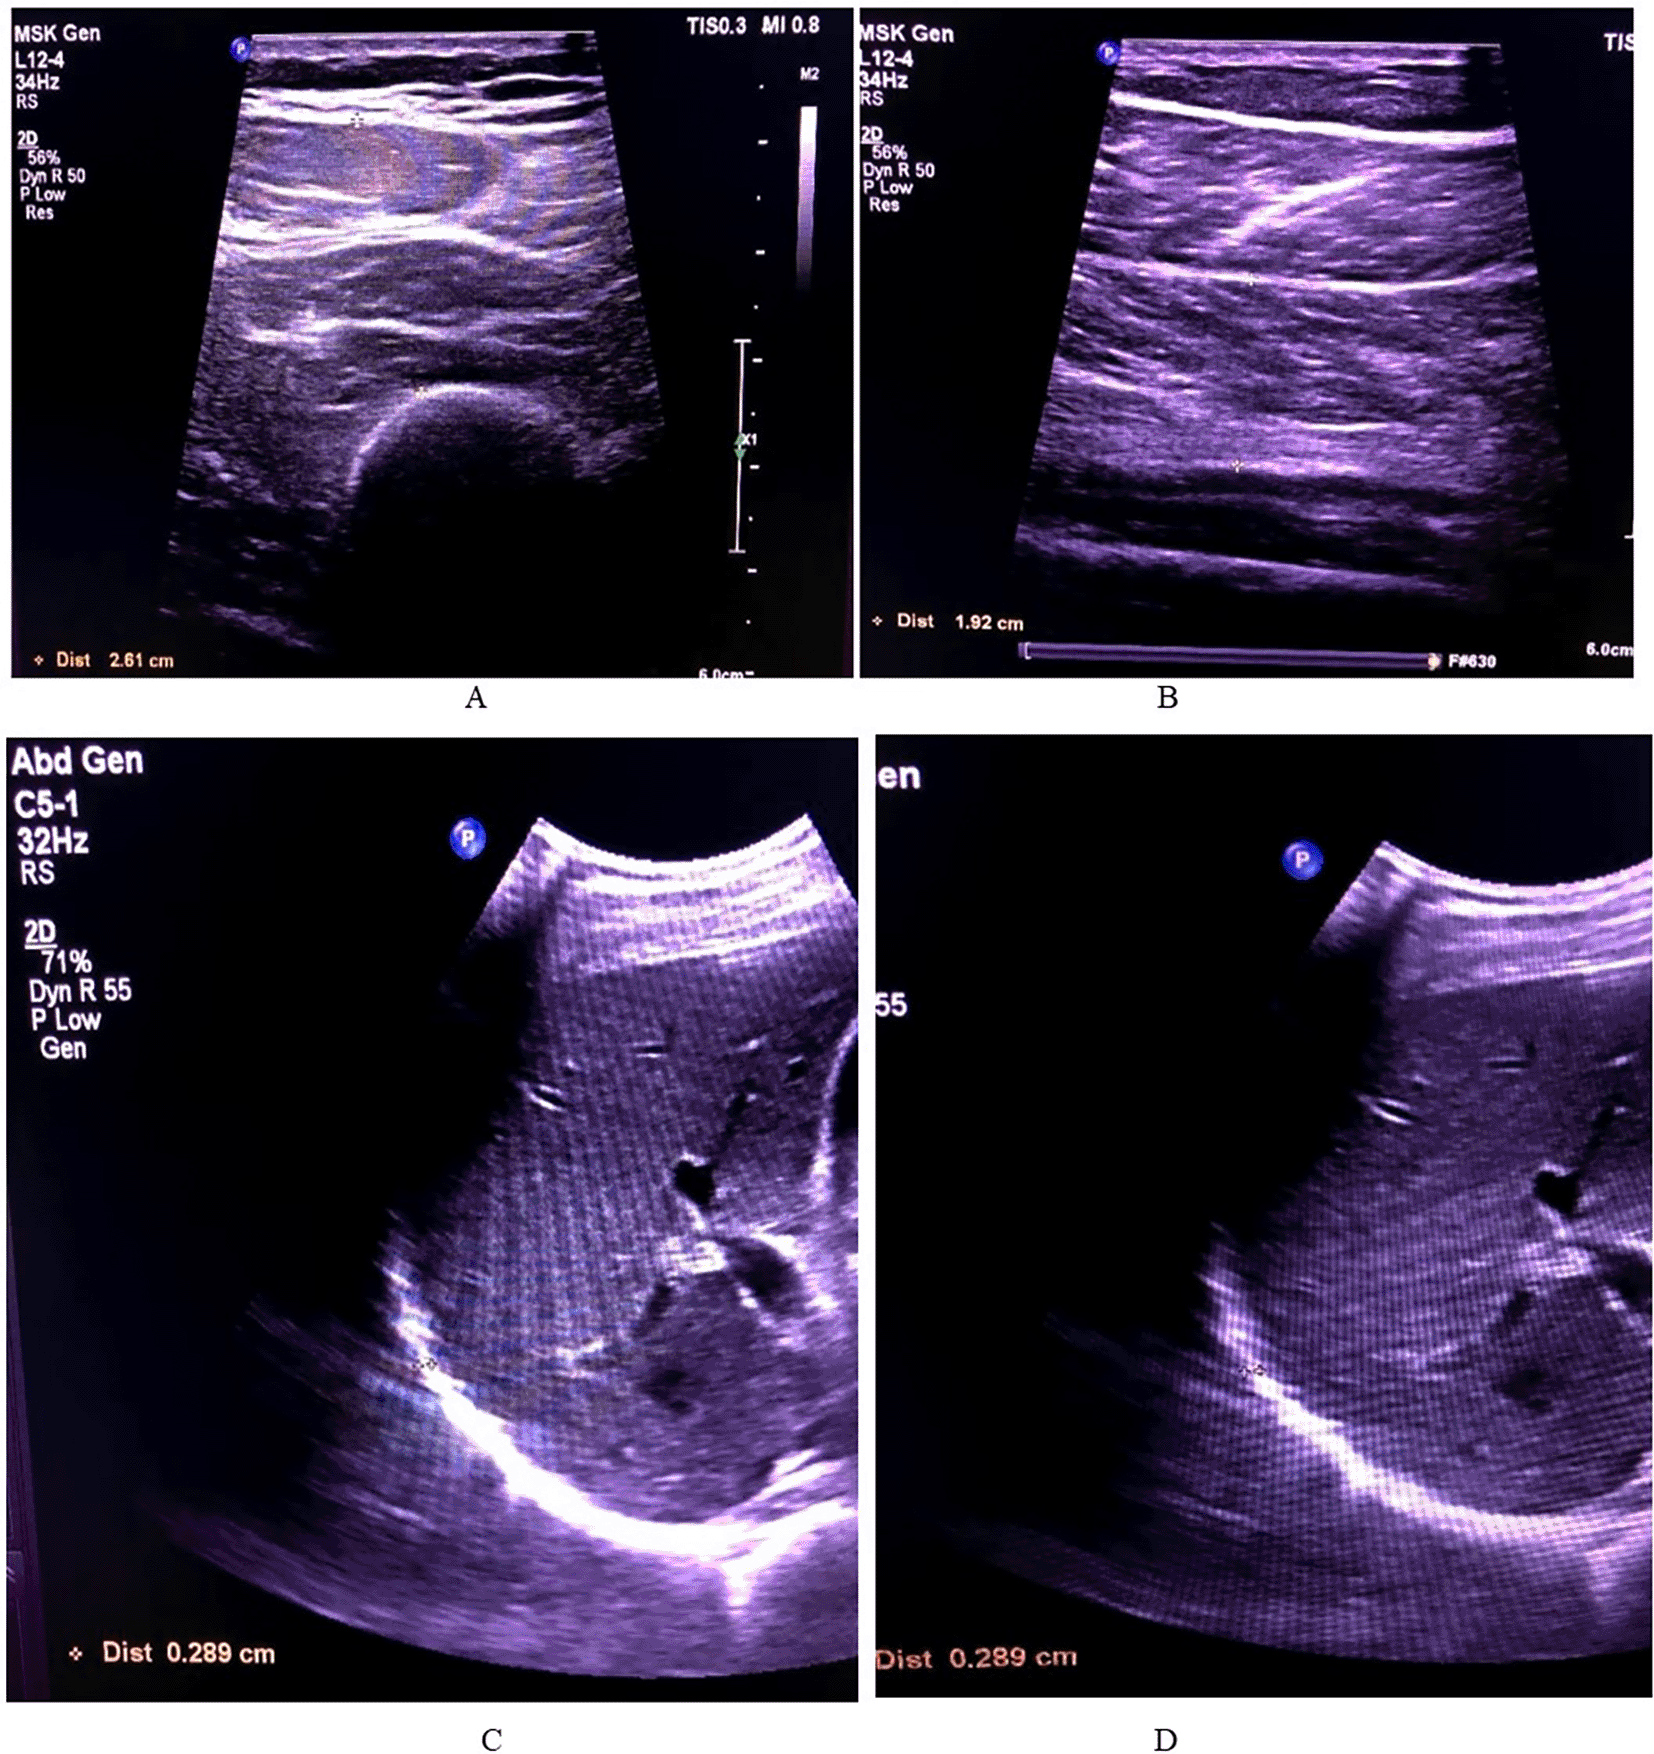

The lower limb muscles measured in this study were the soleus and quadricep muscle (rectus femoris and vastus intermedialis) in both limbs. For measuring the diaphragm, the patient was laid supine and measured at both inhalation and exhalation using the M Mode ultrasonography. The measurement pattern is depicted in Figure 2

Figure 2. The thickness measurements of all the muscles.

A – Soleus, B – Quadriceps (rectus femoris and vastus intermedialis), C – Diaphragm inhalation, D – Diaphragm exhalation.